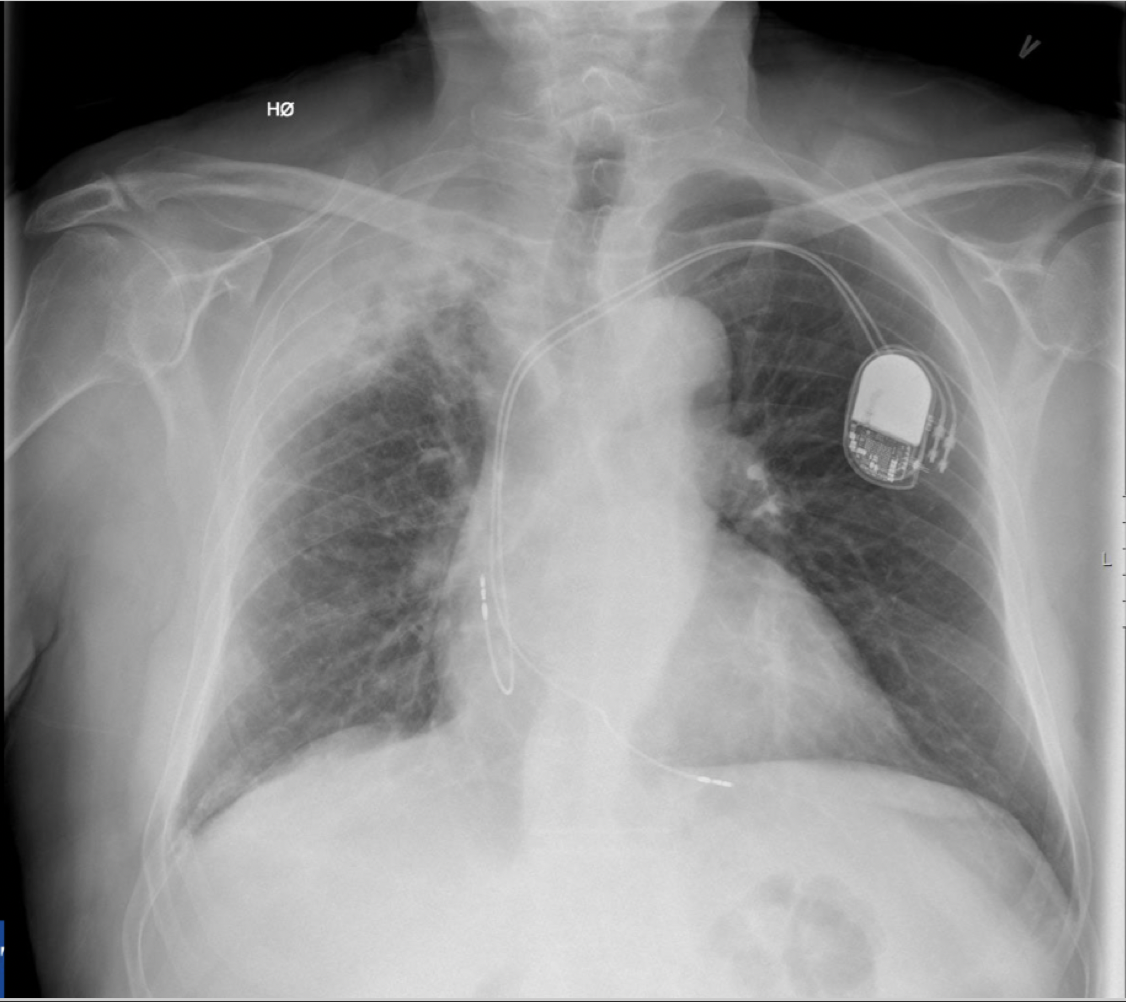

• Rask undersøkelse –> kan gi informasjon om alle organsystemer i thorax (lunger, mediastinum og skjelett + kontrollere posisjoner av tuber, katetre og annet utstyr)

Q

På hvilken måte kan man gi en best mulig beskrivelse av rtg. thorax?

A

1. Tracheadeviasjon?

2. Lungefortetninger

- Pneumothorax

3. Pleuravæske

4. Mediastinum breddeforøket?

- Hilusoppfylninger?

- Normal hjertestørrelse?

- Frakturer i costa eller thoracalcolumna?